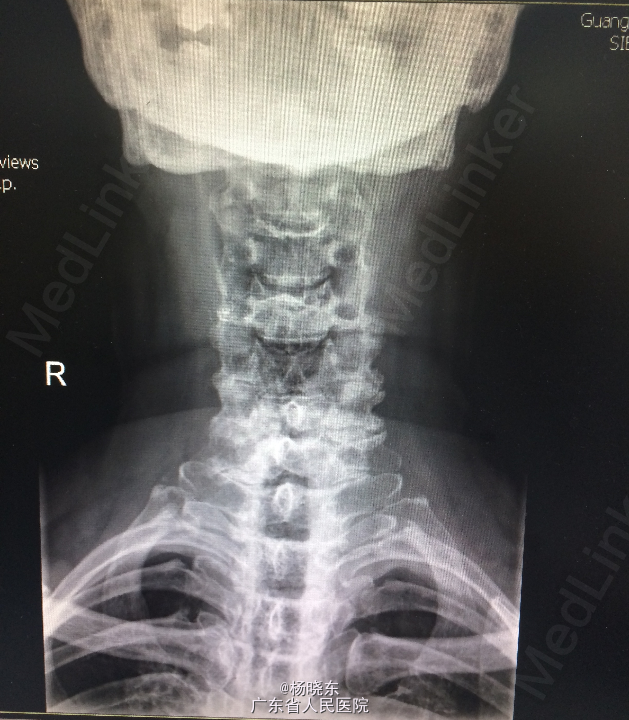

查体:贫血貌,心肺腹查体无特殊。 辅查: 1.全长双下肢长骨正位+尾椎正侧位+肋骨正位+右关节正位+骨盆正位+腰椎正侧位+下胸椎正侧位放射常规照片示:考虑多发性骨髓瘤(多发骨病变)。1、颈椎退行性变 2、腰椎退行性变;多个椎间盘病变;L1椎体轻度压缩性骨折。3、胸椎退行性变。 2.骨髓活检:可见少许造血成分,粒红比例大致正常,均以中晚幼阶段细胞为主,全片可见三个巨核细胞,形态未见明显异常。并可见浆细胞散在。 3.骨髓-外周血涂片:MM-骨髓增生活跃,浆细胞占58.0%,其中原幼浆占53.5%,外周血占2.0%。